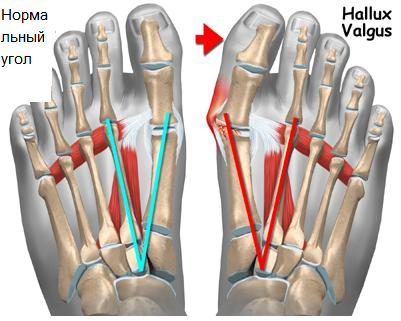

Если Вы посетители эту страницу нашего сайта, значит, у Вас есть проблемы со стопами. Наиболее частой патологией стопы, с которой пациенты обращаются к ортопеду является деформация переднего отдела стопы (поперечное плоскостопие с вальгусной деформацией первого пальца ( шишки или косточки в области первого пальца).

Поперечное плоскостопие может быть как врожденным, так и приобретенным в результате травм, либо различных заболеваний. Причинами являются наследственно-конституциональная предрасположенность, слабость мышечно-связочного аппарата, образ жизни, род занятий, ношение тесной обуви на каблуке.

Хирурги не одно столетие разрабатывают методики лечения вальгусной деформации большого пальца стопы (по Шеде, Ревердену, Ювару, Мейо, Мак-брайду и т.д.). На сегодняшний день в мире известно более 150 методов хирургического лечения данной патологии. Основной принцип оперативного лечения вальгусной деформации большого пальца стопы состоит в том, что проводится иссечение верхушки или края первого плюснефалангового сустава (этой самой шишечки), а также удаление и сопоставление мягких тканей и костей с целью уменьшить боль и восстановить нормальную конфигурацию сустава. Среди существующих операций, при этом, можно выделить физиологичные, то есть те, которые нормализуют своды стопы, оси костей и соотношения в суставах, другие же операции чисто механически устраняют существующую деформацию, не устраняя причины ее развития.